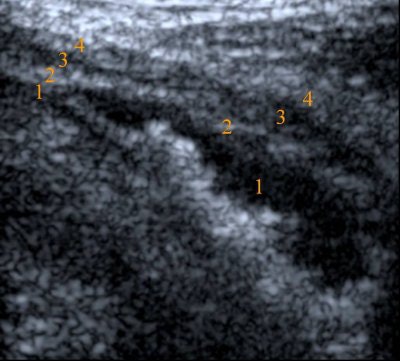

For the intraurethral US exam, the bladder was filled with 250 mL of saline, the catheter was inserted into the bladder, and the external sphincter of the urethra in the area between the middle and distal third of the urethra was identified by its hypoechoic appearance.

| Criteria for staging on high-frequency ultrasound. T1 = invasion of the mucosa (1) and submucosa (2); presence of hyperechoic rim of submucosa. T2a = infiltration of the muscle (superficial -3); no hyperechoic rim of submucosa; muscle layer is not thickened. T2b = infiltration of the muscle (deep -3); no hyperechoic rim of submucosa; muscle layer is not thickened. T3a = infiltration of the perivesical fat (micro -4); thickened. T3b = infiltration of the perivesical fat (macro -4); thickened muscle layer, irregular external wall. T4 = invasion in the adjacent organs. |